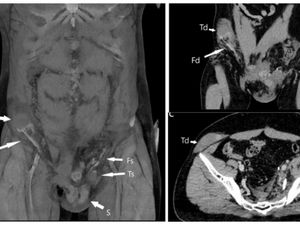

Seorang pria berusia 23 tahun baru-baru ini bikin heboh setelah nekat menancapkan dua paku ke skrotum testisnya imbas disuruh teman khayalan. Begini kisahnya.